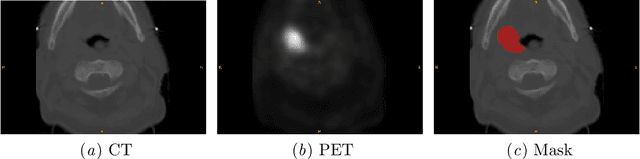

Abstract:Cancer is one of the leading causes of death worldwide, and head and neck (H&N) cancer is amongst the most prevalent types. Positron emission tomography and computed tomography are used to detect and segment the tumor region. Clinically, tumor segmentation is extensively time-consuming and prone to error. Machine learning, and deep learning in particular, can assist to automate this process, yielding results as accurate as the results of a clinician. In this research study, we develop a vision transformers-based method to automatically delineate H&N tumor, and compare its results to leading convolutional neural network (CNN)-based models. We use multi-modal data of CT and PET scans to do this task. We show that the selected transformer-based model can achieve results on a par with CNN-based ones. With cross validation, the model achieves a mean dice similarity coefficient of 0.736, mean precision of 0.766 and mean recall of 0.766. This is only 0.021 less than the 2020 competition winning model in terms of the DSC score. This indicates that the exploration of transformer-based models is a promising research area.